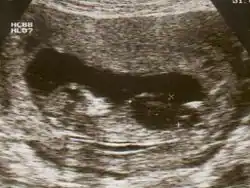

Ultrasound of fetus with Down syndrome showing a large bladder

Ultrasound scan of a fetus with megacystis

Fetal megacystis is diagnosed during pregnancy by ultrasound imaging procedures. Since it can be associated with genetic abnormalities, further ultrasounds and tests may be administered during pregnancy. It may also be diagnosed as megalocystis, and/or termed megabladder, which is the same condition.